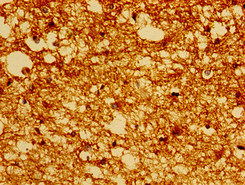

• Immunohistochemistry of paraffin-embedded human brain tissue using CSB-PA859113EA01HU at dilution of 1:100